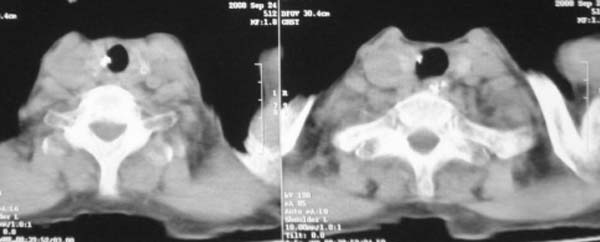

颈部见多枚淋巴结肿大,考虑尘肺继发结核,喉部淋巴结钙化,不除外喉部慢性淋巴结炎、喉淀粉样变及类癌等

颈部多个肿大淋巴结,考虑矽肺并结核

符合矽肺,另外甲状腺可见病变,需强化明确.

考虑尘肺继发结核,喉部淋巴结钙化,不除外喉部慢性淋巴结炎。

双上肺结节融合影,周围有纤维条索影,结合粉尘接触史,首先考虑尘肺。双侧颈部有增大淋巴结,有声嘶表现,肺癌淋巴结转移不能排除。可结合颈部淋巴结活检。